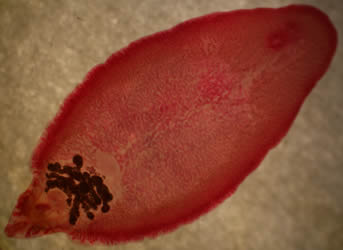

¡Buenos días! En la última entrega del año de nuestra sección de microorganismos quiero hablar de un parásito que pertenece al grupo de los helmintos, a la clase Trematoda, subclase Digneas, voy a hablar de Fasciola hepática.

Como ya os contamos en el primer post de la sección, los helmintos son gusanos, organismos pluricelulares, en el caso de la Fasciola hepática, pertenece al grupo de los gusanos planos, sin sistema respiratorio ni circulatorio, pero con un sistema reproductor muy desarrollado, es hermafrodita.

Tiene dos ventosas a nivel anterior para adherirse a los organismos que va a parasitar, en el caso de Fasciola hepática, se instala en el hígado.